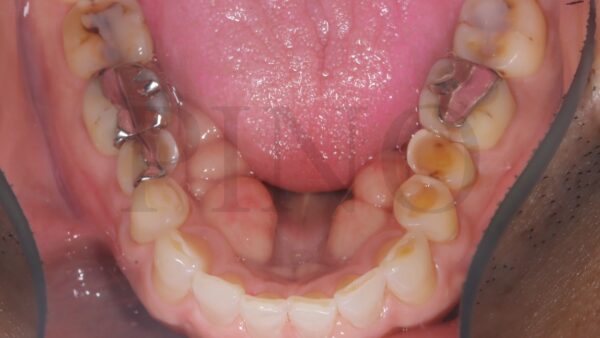

1. 下の歯の内側に骨の膨らみ(骨隆起)がある

下の歯の内側にこのような骨の膨らみがある方、いらっしゃいませんか?

この骨の膨らみは骨隆起と言います。

日常的に食いしばる癖があると、歯にストレスがかかり骨が反応性に成長して厚みが出ている可能性があります!

骨隆起自体は病気では無いため治療をする必要はありませんが、かなりの力で食いしばっている可能性があるため要注意です。